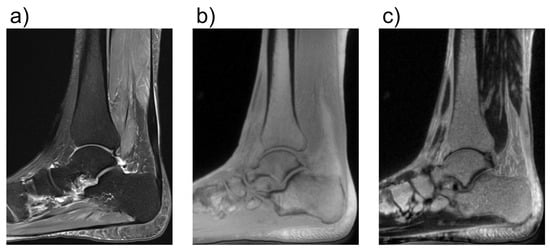

- Fritz, B.; Bensler, S.; Thawait, G.K.; Raithel, E.; Stern, S.E.; Fritz, J. CAIPIRINHA-accelerated 10-min 3D TSE MRI of the ankle for the diagnosis of painful ankle conditions: Performance evaluation in 70 patients. Eur. Radiol. 2019, 29, 609–619. [Google Scholar] [CrossRef]

- Albano, D.; Martinelli, N.; Bianchi, A.; Giacalone, A.; Sconfienza, L.M. Evaluation of reproducibility of the MOCART score in patients with osteochondral lesions of the talus repaired using the autologous matrix-induced chondrogenesis technique. Radiol. Med. 2017, 122, 909–917. [Google Scholar] [CrossRef] [PubMed]

- Albano, D.; Martinelli, N.; Bianchi, A.; Messina, C.; Malerba, F.; Sconfienza, L.M. Clinical and imaging outcome of osteochondral lesions of the talus treated using autologous matrix-induced chondrogenesis technique with a biomimetic scaffold. BMC Musculoskelet. Disord. 2017, 18, 306. [Google Scholar] [CrossRef] [PubMed]